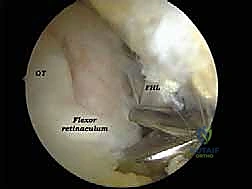

الخطوة 3: الاستكشاف البانورامي (Diagnostic Arthroscopy)

يتم إدخال كاميرا المنظار عالية الدقة (4K) عبر أحد المداخل، بينما تُستخدم الأدوات الجراحية الدقيقة في المدخل الآخر. تتيح الكاميرا للدكتور هطيف رؤية الهياكل الداخلية مكبرة عشرات المرات على شاشة عملاقة، مما يسمح بتقييم دقيق للمفاصل، الأوتار، والأربطة.

* استئصال العظم الزائد (Os Trigonum Excision): يتم فصل العظم الزائد بحذر عن الأنسجة المحيطة واستخراجه بالكامل، مما يزيل سبب الانحشار والألم فوراً.

* تحرير وتنظيف وتر (FHL): إذا كان الوتر ملتهباً ومحاصراً، يتم قطع سقف النفق الليفي لتحريره، وإزالة الأنسجة الملتهبة (Tenosynovectomy) لضمان انزلاقه بحرية.